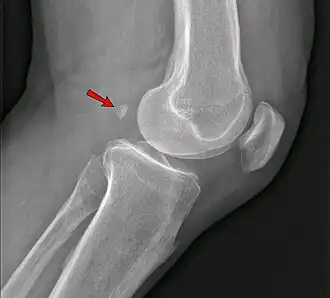

Фабелла — небольшая сесамовидная кость, обнаруженная у некоторых млекопитающих, встроенная в сухожилие боковой головки икроножной мышцы позади латерального мыщелка бедренной кости. Это дополнительная кость, анатомическая вариация, присутствующая у 39 % людей[1][2]. В редких случаях таких костей бывает две или три (fabella bi- или tripartita). Эту кость можно принять за дряблое тело или остеофит. Слово fabella — это латинское уменьшительное от слова faba, означающего «фасоль»[3].

Среди людей фабелла чаще встречается у мужчин, чем у женщин, и у пожилых по сравнению с более молодыми. Существуют большие региональные различия, при этом фабеллы чаще всего встречаются у людей, живущих в Азии и Океании, и наименее распространены у людей, живущих в Северной Америке и Африке. Двусторонние случаи (по одному на колено) более распространены, чем односторонние (по одному на человека), и в отдельных случаях фабеллы в равной степени могут присутствовать в правом или левом колене. Эти данные предполагают, что способность образовывать фабеллу может контролироваться генетически, но окостенение фабеллы может контролироваться окружающей средой[4].

«Фабелла может вызывать заднебоковую боль в колене либо из-за размягчения хряща (chondromalacia fabellae), либо из-за других остеоартрозных изменений на его суставной поверхности»[6].